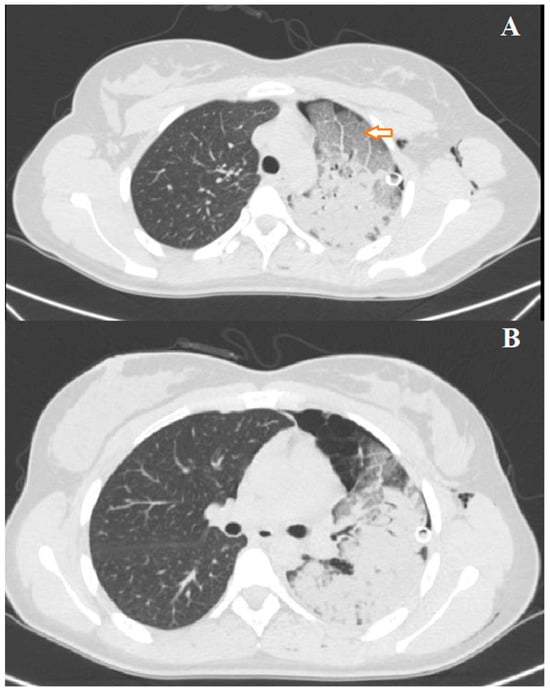

3.3. Case 3